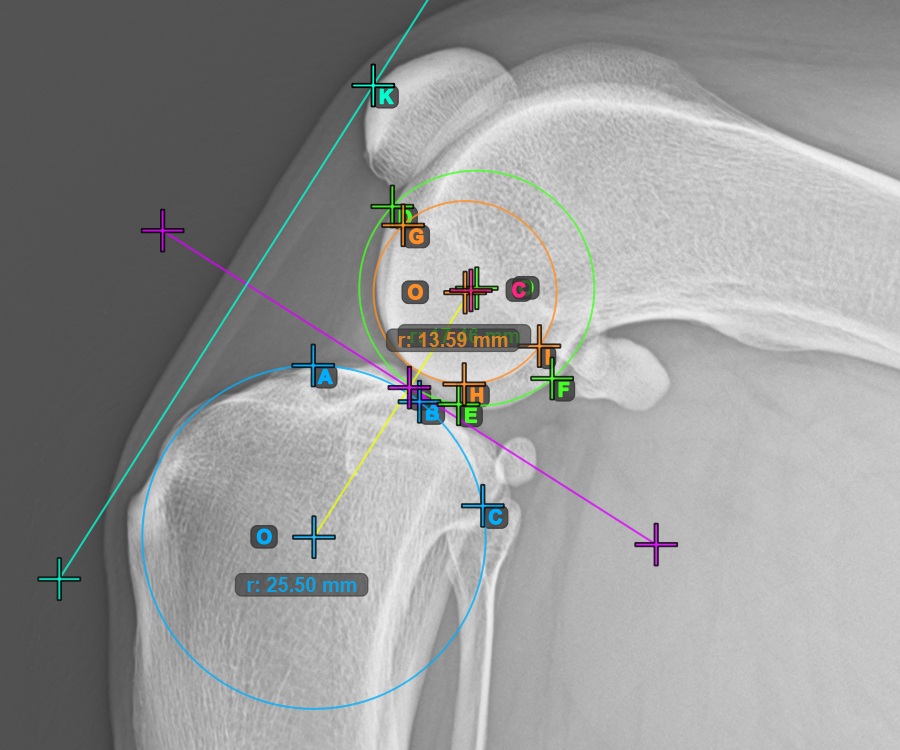

Folytassa a mérést az első Condylus Femoris ízületi felszínén lévő három pont megjelölésével.

Jelölje meg a három pontot a combcsont fő condylusán (Condylus Femoris). A sorrendtől függetlenül ügyeljen arra, hogy megjelölje a legfelső pontot, a legalacsonyabb pontot és a Condylus Femoris középpontját. A három pont alapján a rendszer automatikusan létrehoz egy kört.

A lenti kép az első Condylus Femoris-on elhelyezett három pont tipikus elhelyezkedését ábrázolja.